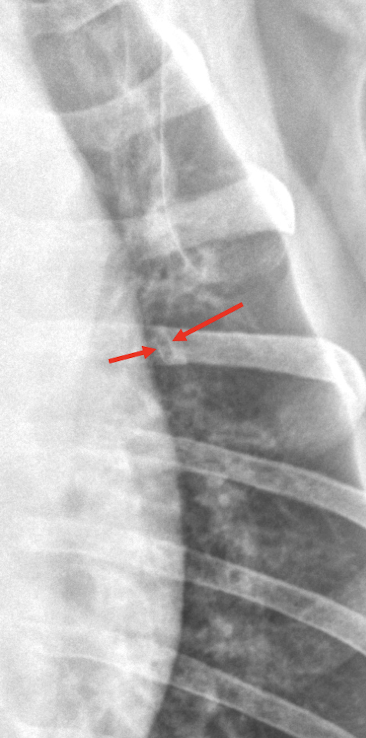

63

Lung Pattern?

Pneumothorax

67

Pneumothorax *Arrows = atelectasis*